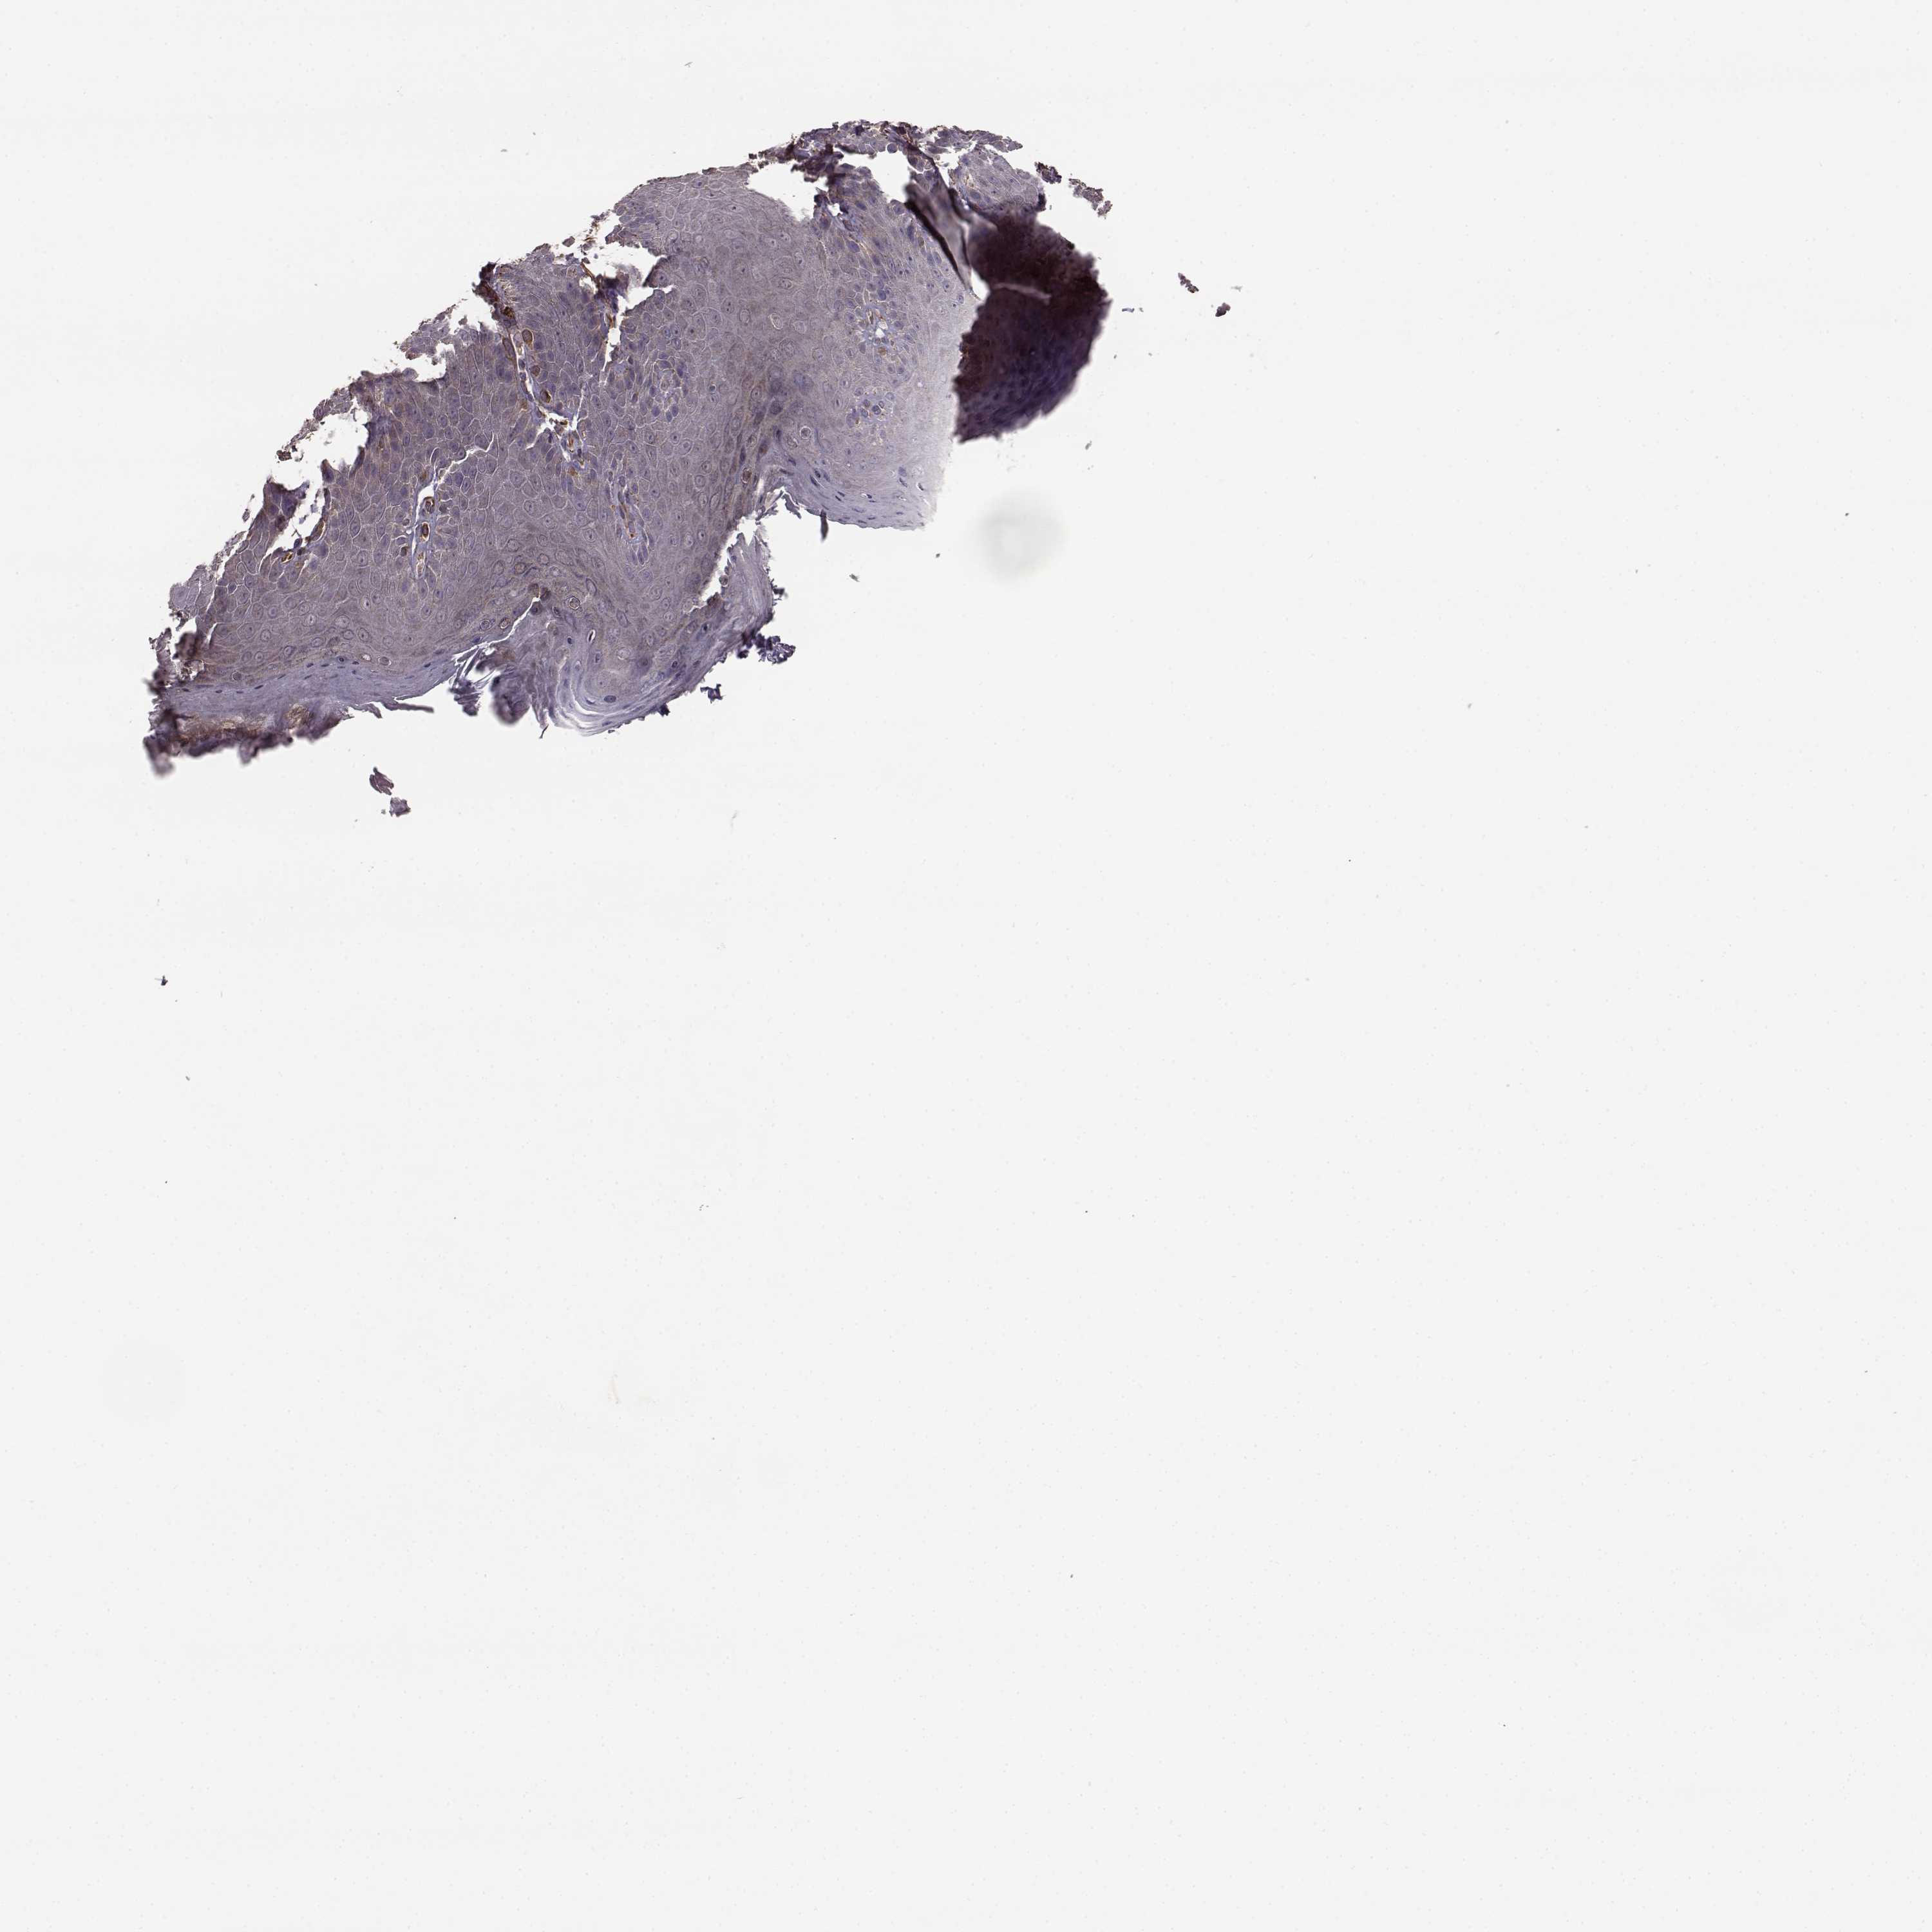

SKIN 1 - Antibody stainingi

Antibody staining in the annotated cell types in the current human tissue is reported as not detected, low, medium, or high, based on conventional immunohistochemistry profiling in selected tissues. This score is based on the combination of the staining intensity and fraction of stained cells.

Each image is clickable and will lead to virtual microscopy that enables deeper exploration of all samples and also displays staining intensity scores, fraction scores and subcellular localization as well as patient and tissue information for each sample.

Antibody HPA032001

Langerhans Medium

Fibroblasts Not detected

Keratinocytes Not detected

Melanocytes Not detected